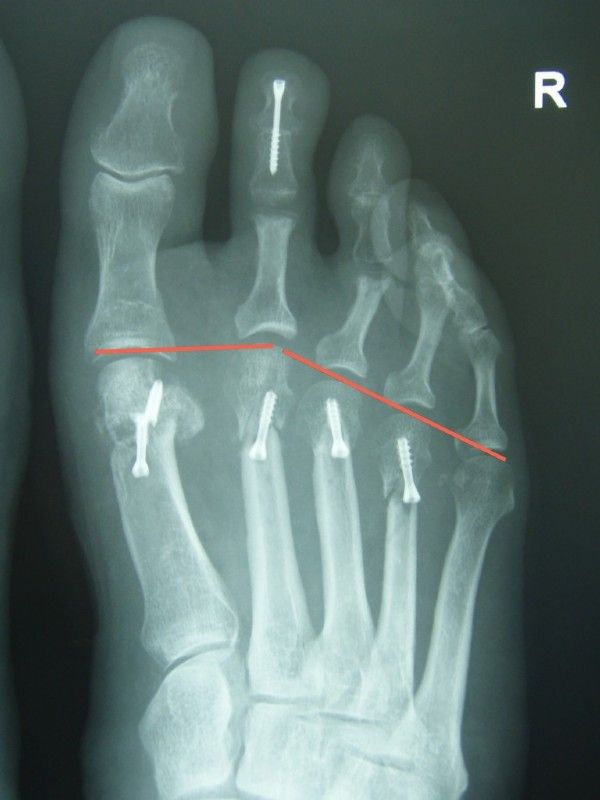

Here is another example, with a drawn "metatarsal index" (or parable or Alignment)

Left: the metatarsals II, III and IV are too long and do not make the necessary parabola, which results in too much burden, pain and calluses in the ball area.

Right: So it should be: After the operation, the X-ray shows the metatarsals. The I metatarsal is the longest, the II is about the same length or slightly shorter, the III. even shorter, etc.